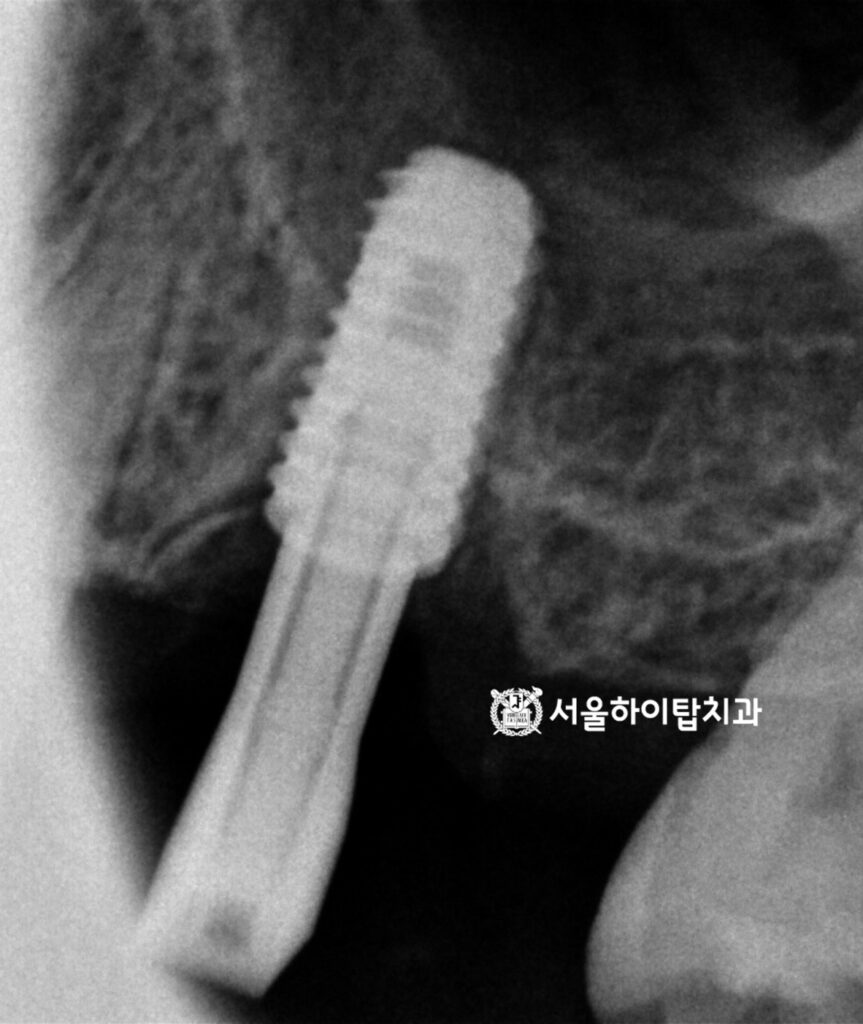

이제 간석역 치과 에서 문제가 되는 부위를 좀 더 자세히 살펴보겠습니다.

마찬가지로 임의로 표시해 둔 선을 기준으로 보면,

치조골이 대부분 소실되어 잇몸이 치아를 겨우 지탱하고 있는 상태임을 확인할 수 있습니다.

또한 방사선 사진에서도 확인될 정도로

교합면 마모가 심하게 진행되어 있으며,

치아의 mesial(근심면) 부위에는 파절 소견이 관찰됩니다.

이처럼 골 소실이 진행된 상태에서 마모와 파절까지 동반된 경우에는,

자연치를 보존하더라도 장기적인 안정성을 기대하기 매우 어렵습니다.

특히 잇몸뼈의 지지가 충분하지 않은 상태에서는

보존이나 보철 치료를 시행하더라도 재파절이나 염증 재발의 가능성이 높아,

발치를 통한 감염원 제거가 불가피한 상황으로 판단되는 경우가 많습니다.

따라서 무리하게 유지하기보다, 임플란트를 통해

저작 기능과 구조적 안정성을 회복하는 것이

예후가 좋은 치료 방향으로 보여집니다.